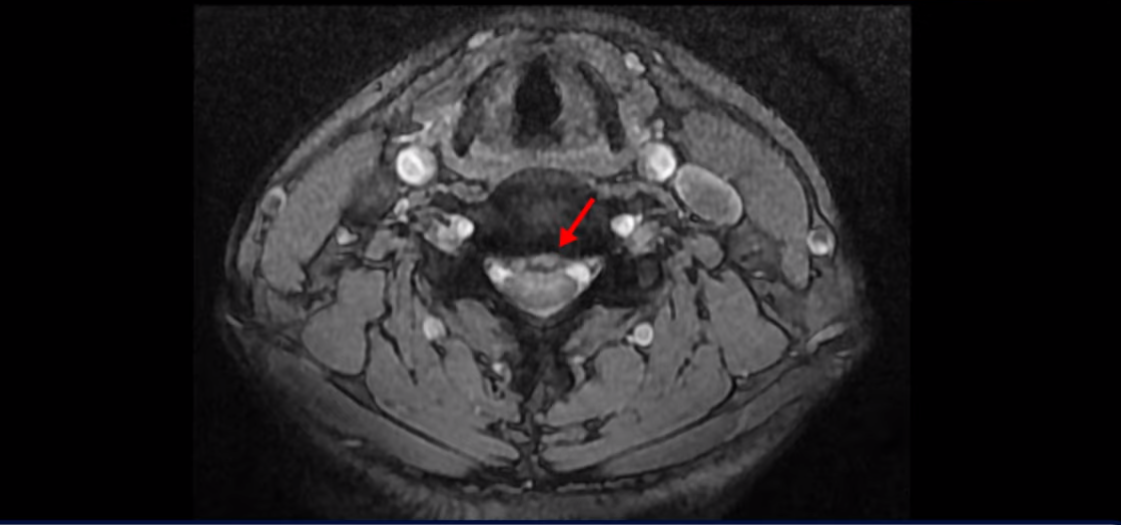

중앙 오른쪽으로 수핵이 밀려 나와있고 밑으로 흘러 내려가 있습니다.

그런데 이 환자분의 방사통은 왼쪽 어깨와 팔입니다. 그래서 이 4번 5번 디스크 파열은 왼쪽 방사통의 원인이 아닌 걸로 보입니다. 6번 7번을 보면 디스크가 왼쪽으로 밀려 나와 있고, 뼈도 자라나 있습니다.

이렇게 뼈가 자라나 있으니까, 신경가지가 빠져나가는 추간공을 보면 여러 마디가 다 좁아져 있습니다.